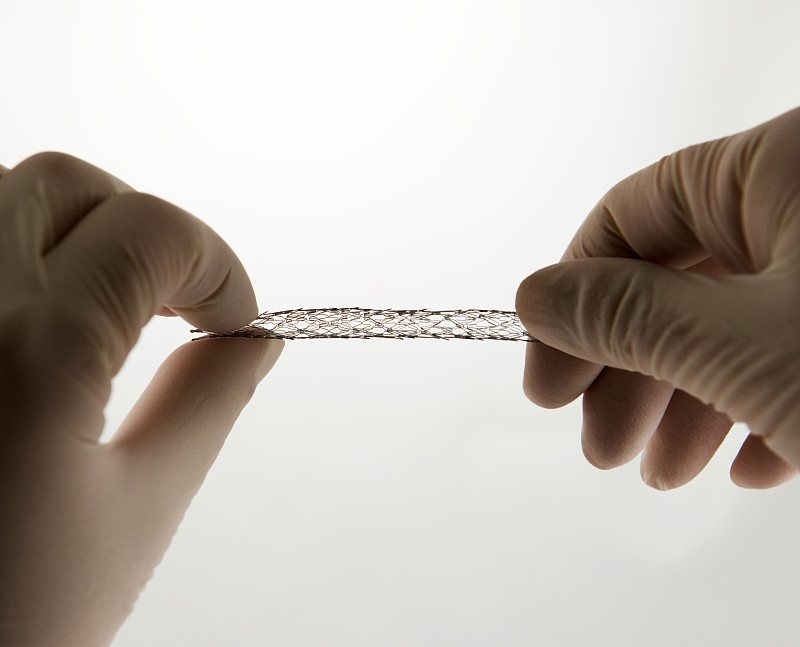

血管内手术用支架详情

JPG

血管内手术用支架详情

JPG